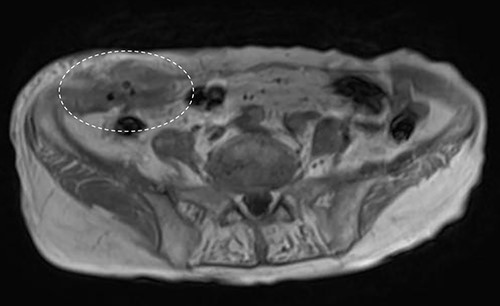

A 90-year-old woman was referred to our hospital complaining of a painful mass located in the right lower quadrant of her abdomen. She had a history of acute appendicitis, for which she underwent an appendectomy approximately 70 years prior to the current consultation. She first noticed the pain 6 months prior to consultation. In the interim, the pain gradually worsened. Upon physical examination, a palpable tumor was present below the appendectomy scar. Yellowish pus was removed from the skin over the tumor (Fig. 1). Computed tomography (CT) revealed a tumor in the abdominal wall under the surgical scar of the appendectomy (Fig. 2a). The tumor was 60 mm in width and contained a linear-shaped agent, which was thought to be a foreign body, such as a surgical needle (Fig. 2b and c). Magnetic resonance imaging (MRI) also revealed a low-signal nodule on a T1-weighted image (Fig. 3). Laboratory test results revealed no signs of inflammation. Pus culture revealed no pathogens.

Abdominal CT demonstrated a tumor in the abdominal wall, which extended to the surface of the body (a, encircled); the tumor was 60 mm in width and contained a linear shaped agent; sagittal (b, encircled) and coronal (c, encircled) views.

Abdominal MRI showed a low-signal nodule on T1-weighted image (encircled).